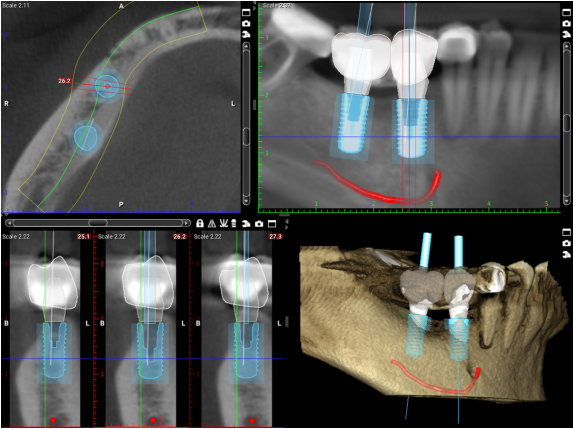

מכשיר הדמיה ממוחשבת CT הוא מכשיר פורץ דרך אשר יישומיו בעולם רפואת השיניים מאפשרים כיום לכל רופא שיניים מקצועי ומיומן לקבל תמונה מלאה ומדויקת יותר של חלל הפה והשיניים בפיו של כל פציינט.

צילומי ה-CT מאפשרים לרופא השיניים לראות את הלסת כולה בצורה של שכבות על גבי שכבות ולקבל ניתוח מעמיק יותר של מצב השיניים בפה והמבנה האנטומי המדויק של עצם הלסת.

בצורה כזאת יכול רופא השיניים המשתמש בשיטה, לדעת במדויק היכן יש למקם את השתלים החדשים בצורה מדויקת כך שלא יפגעו בתעלות העצב ובסינוסים הנמצאים בחלל הפה ולקבל נתונים חשובים על מצב הלסת כמו: עובי העצם, רמת דחיסות וכו'.

- ביצוע CT והכנת סד כירורגי, מעין פלטה עשויה פלסטיק עם חורים במקומות בהם ימוקמו השתלים להשלמת התמונה לפני התחלת ההשתלה.